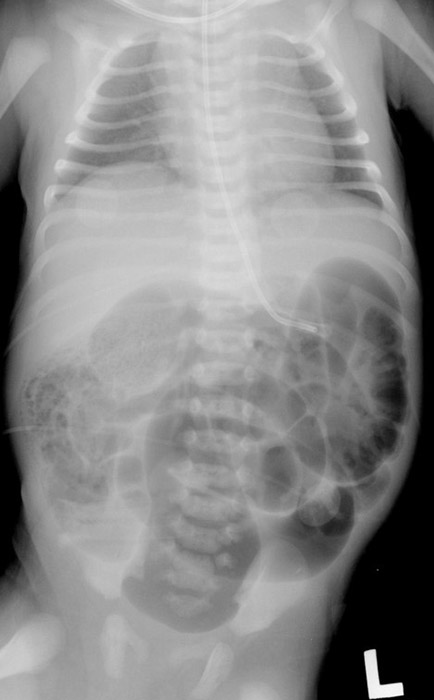

Where does volvulus most commonly occur?

In the cecum and sigmoid colon. (image shows cecal volvulvus)

The cecum twists on its long axis and often displaces upward and to the left.

Bowel obstruction and compromised blood supply.

What can compromised blood supply lead to in volvulus?

Necrosis and gangrene.

Why can volvulus cause peritonitis?

Obstruction can cause severe distension leading to bowel perforation.

What are common symptoms of volvulus?

Severe abdominal pain, vomiting, and abdominal distension.